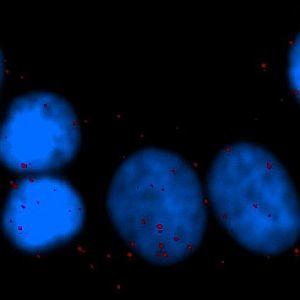

One field of view of the original cell line image (scaled down to fit this space).

The number of in situ PLA signals per nuclei was counted by automated image analysis. Fully automated nuclei delineation was initiated by identifying cell nuclei using the signal from the nuclear Hoechst staining (blue). Touching nuclei were separated using a combination of distance transformation and watershed segmentation. In situ PLA signals were counted by enhancing point-like signals and defining a true signal as a local intensity maximum above a background threshold.

PLA plus and minus probes (containing the secondary antibodies conjugated with oligonucleotides) were added and incubated at 37°C for 2 h. Further oligonucleotides were added, to allow hybridization with PLA probes and ligase. The DNA was then amplified and detection carried out using the 563 detection kit (including Hoechst 33342 dye nuclear staining), resulting in red fluorescence signals. Finally, the slides are mounted with Vectashield mounting media (Vector Lab., Inc., Burlingame, CA, USA).